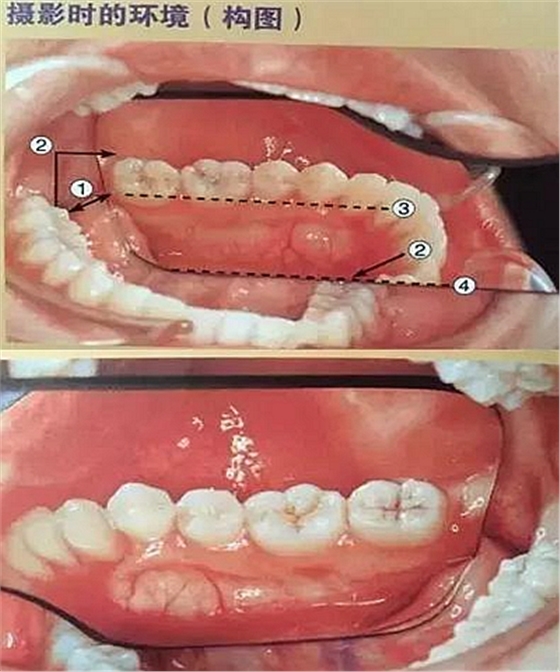

五、頰側(cè)面攝影

口腔攝影方法與技巧

①拿掉攝影側(cè)的口角拉鉤

②輕輕拉住非攝影側(cè)的口角拉鉤

③調(diào)整患者面部的方向(拍右側(cè)向右轉(zhuǎn),拍左側(cè)向左轉(zhuǎn))

④反光板遠(yuǎn)離牙列

⑤牙列在反光板中央位置為好

⑥反光板邊緣與咬合平面平行

⑦反光板開(kāi)口角度盡可能大